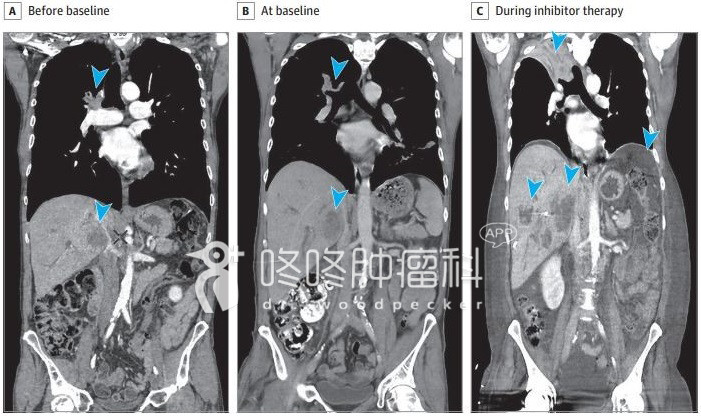

最新的研究数据,是上周发表在JAMA oncology杂志上的汇总分析。406名晚期非小细胞肺癌患者,接受PD-1抑制剂治疗。64%的患者是男性,46%的患者年龄不小于65岁,72%的患者是非鳞非小细胞肺癌,中位随访一年多。406名患者中,以接受治疗后肿瘤生长速度加快,且加快的比例超过50%为爆发进展。那么,爆发进展的患者人数是56人,发生率是13.8%。不过,该研究小组也观察到另外有19名患者一开始也满足了爆发进展的定义,但是后来肿瘤又神奇般地缩小、消退了,也就是说即使一开始被定义为发生了爆发进展的患者中,依然有4.7%的患者属于“假进展”。下图是一个发生爆发进展的患者,接受治疗前后的影像学片子,肿瘤已经用蓝色箭头标出。

图4:爆发进展患者影像变化